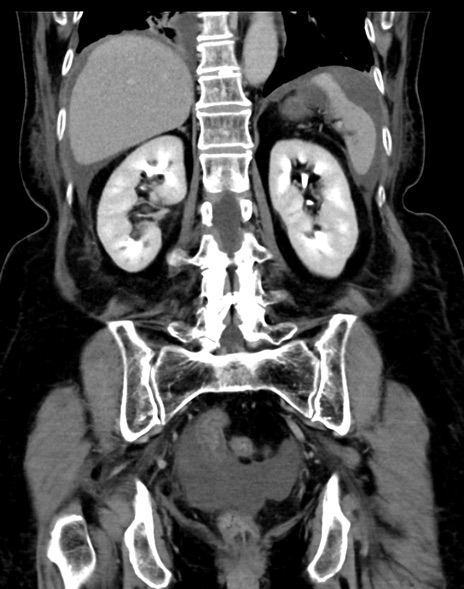

症例13 CT(冠状断像)1日半後